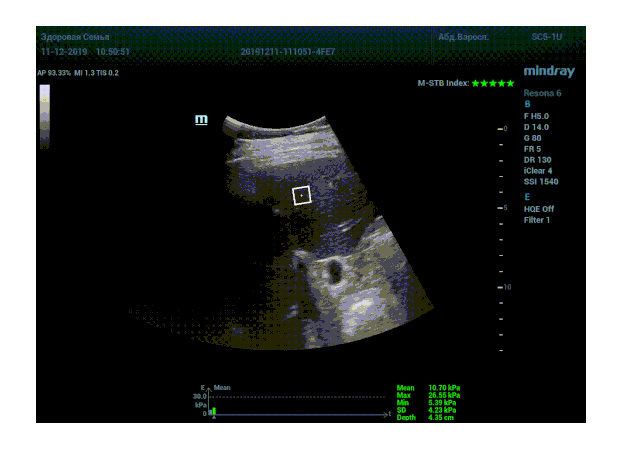

Определение плотности печени. Не ошибся ли оператор при измерении эластических свойств печени? Для оценки критериев качества предусмотрен индекс MBT, который покажет насколько «твердой» была рука оператора и двигалась ли печень. При MBT 5* рука тверда и показатели достоверны. Для оценки качества результатов используется IQR индекс, отображающий колебания показателей в точке измерения при расчете медианы. Показатели при IQR <30% считаются приемлемыми. Техника сканирования через межреберные промежутки требует размещение окна интереса на несколько сантиметром ниже капсулы, для исключения эффекта реверберации. Установка ROI на паренхиму без захвата сосудов, для исключения погрешностей измерения.